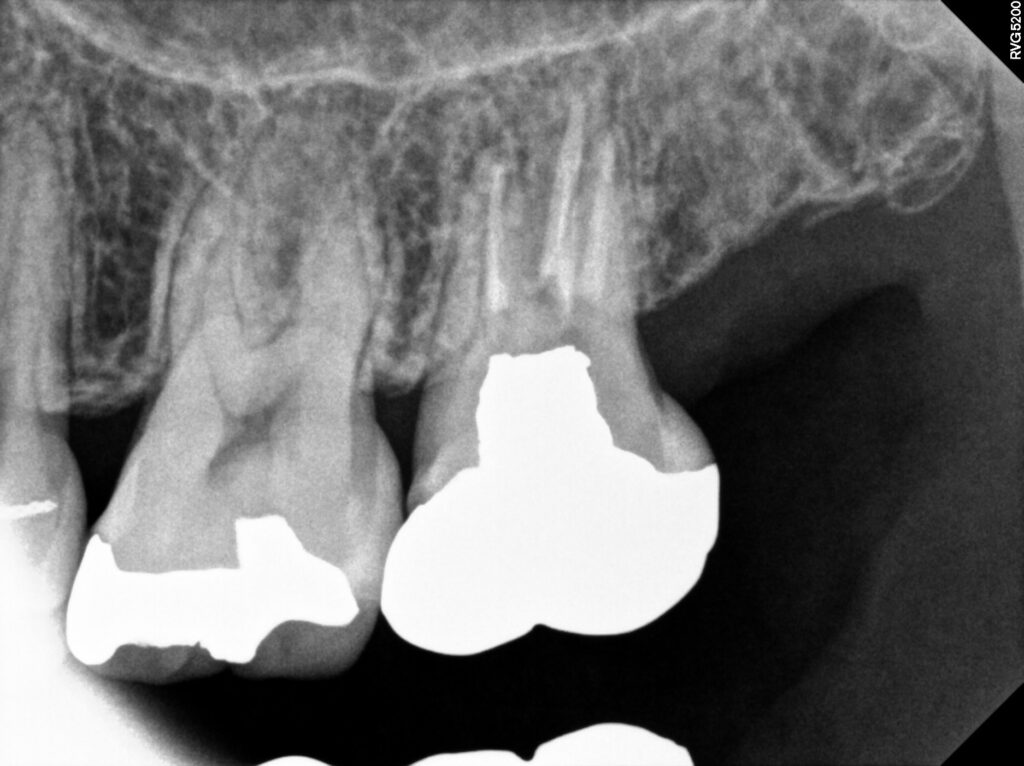

이어서 2024년에 왼쪽 위 가장 안쪽 어금니에

통증이 있어 타 치과에서 재신경치료가 어렵다고 하여

발치권고를 받으셨으나 광화문치과에서

재신경치료를 진행하셨는데요.

잘 맞지 않았던 기존 보철물을 제거하고

내부의 단단한 재료인 코어부터 제거하여

다시 재충전후 보철을 진행하여 현재까지

통증 없이 현재까지 잘 유지하고 계십니다.